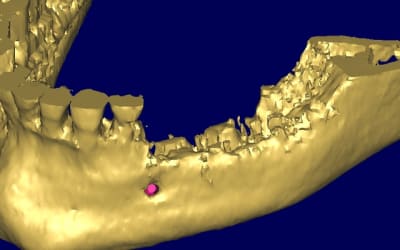

quelques images en 3 D...

Bernard 3d uwkkkv - Eugenol

Bernard 3d  2  cbjwkc - Eugenol

Bernard 3d1 tranjs - Eugenol

Bernard 3d2 egud68 - Eugenol

Bernard 3d3 kd3ilv - Eugenol

Bernard 3d4 iyukqz - Eugenol

Bernard cross section apfhj5 - Eugenol

Bernard cross section  2  ctt7jw - Eugenol

Bernard overview edbft1 - Eugenol

Bernard overview  2  nlgyly - Eugenol

Bernard panoramic l8hei0 - Eugenol